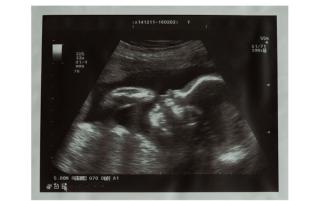

V skutočnosti v 22. týždni začína dieťa v maternici spoznávať hlasy; jeho mozog sa rýchlo vyvíja a cíti dotyk. Dieťa v tomto období môže cítiť aj bolesť.